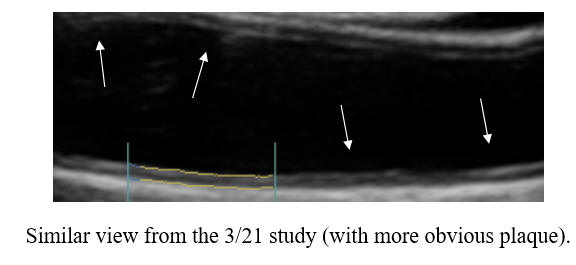

IK, then 57 years-of-age, in 7/06 underwent three-vessel bypass surgery. Health aware and highly motivated, ME put himself on a comprehensive risk factor reduction program, and in 5/08, ME's mean IMT was actually below average-for-age and only mild carotid plaque was seen, with little change two years later. IK developed the great habit of swimming vigorously, three days a week

In early '23, cyclodextrin therapy was initiated, and after 60 doses IK was back in the pool, swimming full force. Hemorrhoidal irritation became and issue, prompting IK to switch to twice a week dosing. After roughly 180 doses (six boxes) through summer '24, IK's carotid study was repeated. The plaque progression identified between '10 and '22, was reversing! Twice a week maintenance cyclodextrin will be continued, along with IK's prior anti-atherosclerotic regimen, and we will repeat his carotid study in two years time.

Baseline Study in 3/21 Post-Cyclodextrin therapy in 3/23